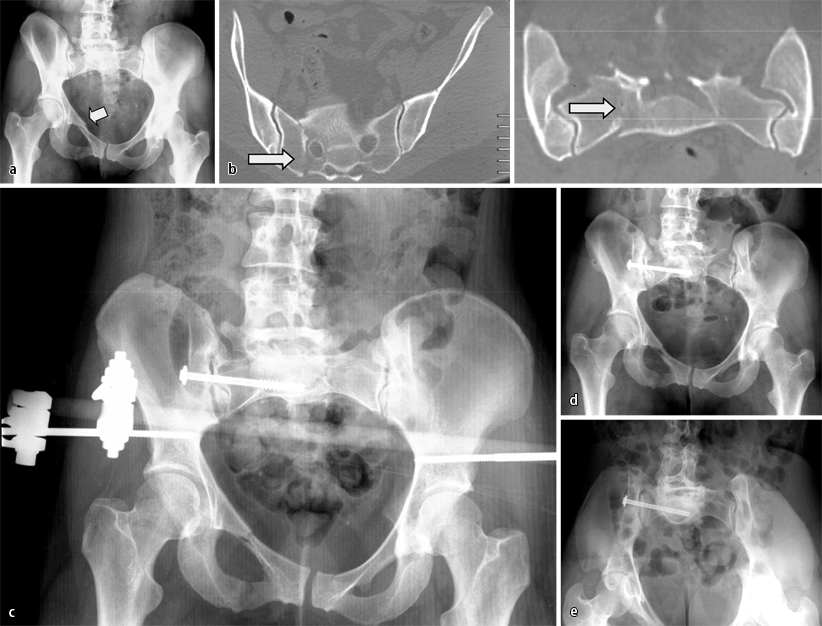

Die für die Stabilität des Beckenrings relevanten Strukturen liegen dorsal (Fall 3, Abb. 3). Wird ein aufnahmetechnisch unzureichendes und somit nicht aussagefähiges Bild als solches akzeptiert, ohne dass die Entscheidung zur weiterführenden Bildgebung (CT) bei entsprechender Anamnese und Klinik fällt, können Verletzungen der Iliosakralgelenke und des Sakrums (zumeist B-, aber auch C-Verletzungen) übersehen werden (Fall 3, Abb. 3). Dies bedeutet nicht, dass „vorsichtshalber“ zum Ausschluss einer Schädigung der posterioren Beckenringstrukturen grundsätzlich ein CT angefertigt werden sollte, da dies beim jungen Patienten zur hohen Strahlenbelastung der Gonaden, bei der rasch zunehmenden Zahl älterer und geriatrischer Patienten zu einer Überdiagnostik ohne therapeutische Konsequenz führt. Gerade bei Letzteren ist es ratsam, im Zweifelsfall einen Mobilisationsversuch zu unternehmen und bei persistierenden Beschwerden unter ausreichender Schmerzmedikation und mangelndem Mobilisationsforschritt ein CT in der 2. Woche nach dem Trauma durchzuführen [13].

Fall 3, 24-Jähriger mit isolierter Beckenringverletzung AO 62C1.3, a unzureichende a.-p. Aufnahme des Beckens, b CT mit koronarer Rekonstruktion: C-Verletzung mit vertikalem Versatz, Abriss des Querfortsatzes von LWK5 rechts, mehrfragmentärer Stauchungsfraktur des Sakrums, c offene Reposition, weitere Erläuterungen s. Kasuistik

Fall 3

Bei dem 24 Jahre alten männlichen Patienten war es bei einem Motorradunfall zu einer isolierten Beckenringverletzung (AO 62C1.3) gekommen. Die a.-p. Aufnahme des Beckens (Abb. 3 a) war lagerungs- und aufnahmetechnisch unzureichend. Die CT-Aufnahmen mit koronarer Rekonstruktion belegten eine C-Verletzung mit vertikalem Versatz sowie Abriss des Querfortsatzes von LWK5 rechts und eine mehrfragmentärer Stauchungsfraktur des Sakrums (Abb. 3 b).

Die Versorgung erfolgte durch offene Reposition der Sakrumfraktur mit winkelstabiler Platte und spinopelviner Transfixation bzw. supraazetabulärem Fixateur externe.